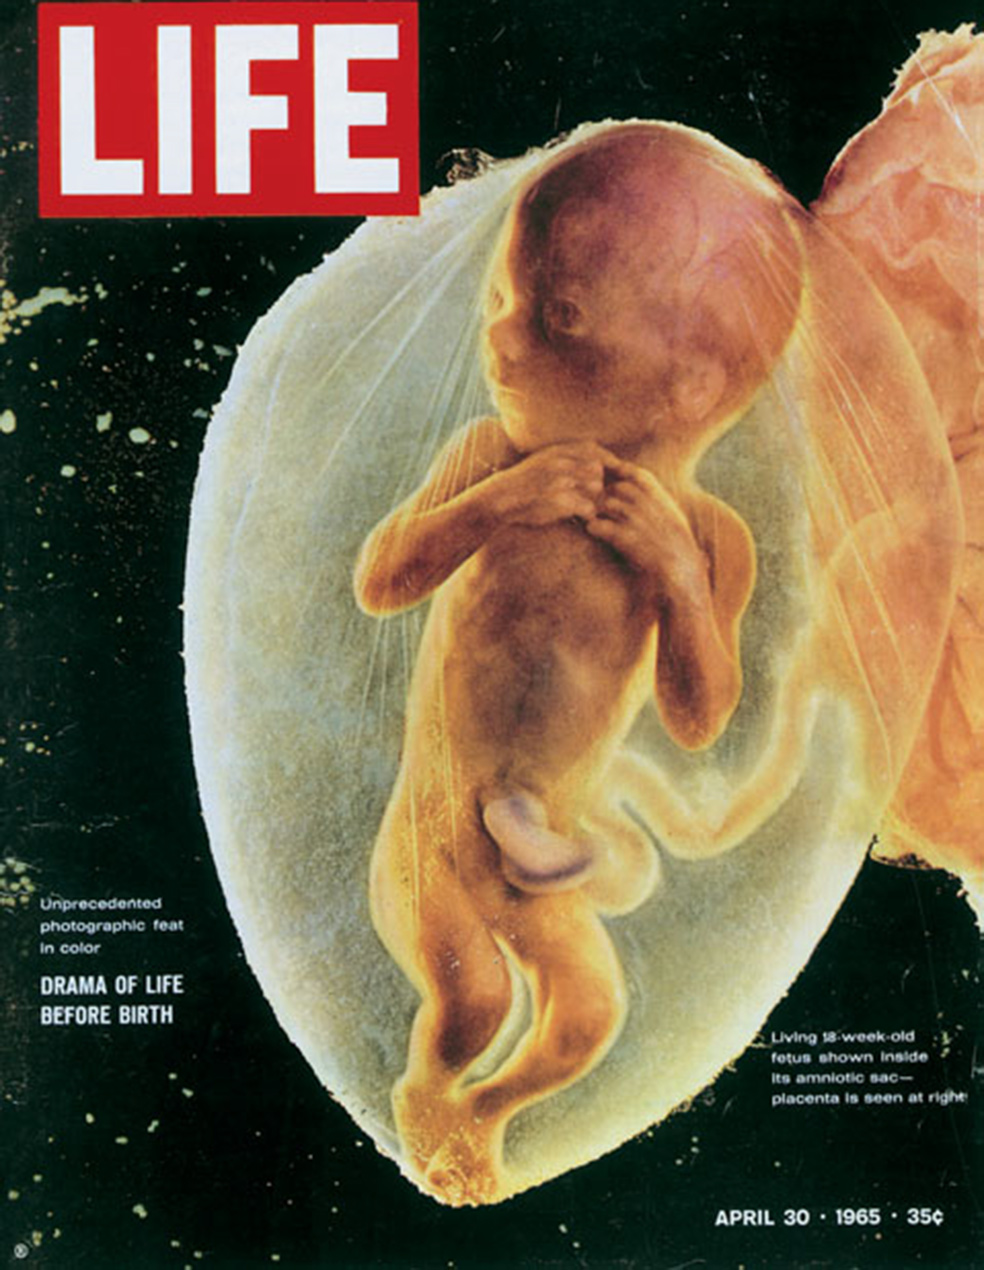

En la primavera de 1965, la revista Life mostraba en su portada la imagen de un feto humano, rebosante de vida, en el interior del útero de su madre. Con sólo 18 semanas de gestación, el primer feto en convertirse en portada de una revista resultó ser un modelo nato. El actorcillo más pequeño de la historia sabía exactamente qué hacer con las manos: las unió en lo que parecía una plegaria. En un par de días se vendieron millones de ejemplares de la revista. El milagro de la vida pareció aún más milagroso. Respecto a Lennart Nilsson, el risueño sueco que había tomado la fotografía, su nombre se convirtió en una referencia mundial y sus libros, como Life y Nacer, la gran aventura, se han vendido por millones en todo el mundo desde entonces.

Una portada para la historia

Portada de la revista Life de 1965 con la imagen fetal fotografiada por Nilsson, Pocos años después, los norteamericanos consiguieron llevar a su primer hombre a la Luna, y Neil Armstrong pudo articular su tan cacareada frase del pequeño paso para el hombre y el gran paso para la humanidad. Lo mismo podía haber dicho el propio Nilsson, en el caso de que hubiera sido americano o de que le gustaran mucho las frases grandilocuentes. Nilsson había descubierto, entre otras cosas, que la vida al otro extremo del microscopio era, en el fondo, bastante parecida a la vida al otro extremo del telescopio: la galaxia y el átomo son universos paralelos. Y uno de los motivos por los que el feto humano que apareció en la portada de la citada revista tuvo tantísima repercusión fue que este pequeño ser humano, flotando en la oscuridad de la placenta en desarrollo, parecía un astronauta dándose un paseo por el espacio.